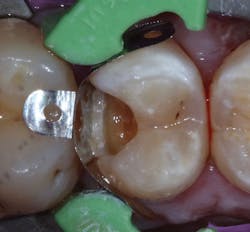

When a carious lesion and the Class II cavity preparation extend near to or apical to the cementoenamel junction, the sandwich technique can be used. The technique is described as a layering of various restorative materials within the cavity preparation. It involves placing RMGI at the base of the cavity preparation, followed by curing and the addition of composite restoratives to complete the restoration. If the remaining layers of composite resin completely encase the RMGI, it is considered a "closed" sandwich technique. If the RMGI is exposed to the oral environment at the base of the restoration, it is considered an "open" sandwich technique (figures 1a and 1b).

Figures 1a and 1b: RMGI sandwich techniques

This technique is not new and was originally proposed by Suzuki and Jordan. (4) According to Liebenberg, "The open-sandwich technique allows the least amount of microleakage of the various direct restorative options currently available." (5,6) This occurs because traditional composite bonding at the cavosurface and interproximal sites often have a complex combination of substrates that include enamel and varying levels of dentin, depending on the depth of the lesion. Liebenberg continues, "For dentin bonding, it appears far easier to achieve a seal than to maintain it, and in vivo studies have confirmed that resin-dentin bonds degrade in the oral cavity." (5,7)